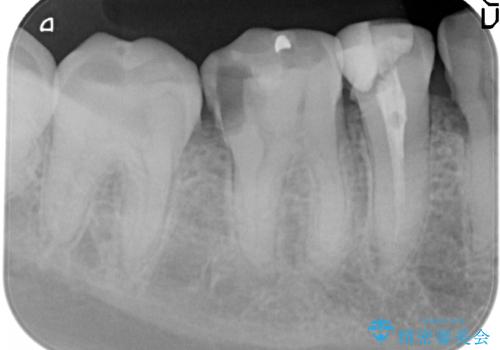

- 放置してしまった虫歯治療を希望され来院されました。

虫歯を徹底的に除去したのち、長期的に安定し審美的なジルコニアクラウンで機能回復を図ります。